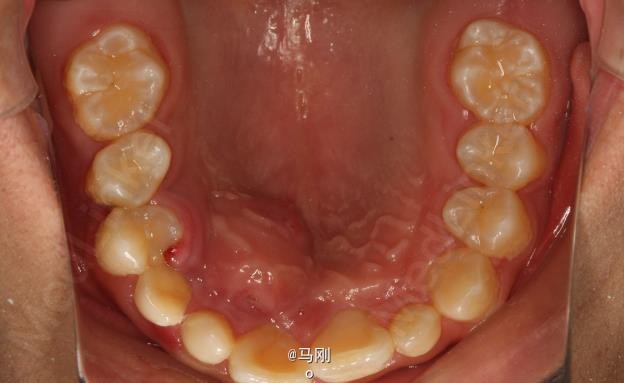

患者、李xx、男、14岁。主诉:牙齿排列不齐,要求正畸治疗。平素体质一般,无药物、食物过敏史,无高血压、心脏病等系统性疾病。

查体 辅查

专科检查:右侧乳尖牙滞留,13腭侧粘膜轻度肿胀。CBCT检查:13位于腭侧。